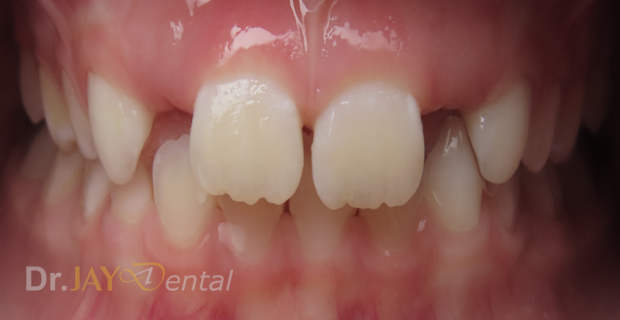

CASE 8

Patient had open bite and severe mouth breathing . At our office , patient went through myofunctional therapy , expansion of upper and lower jaw and aligning of teeth . No extractions needed and orthodontics was focused on airway, correcting habits and giving importance to the holistic health of patient. Patient’s mom extremely happy with the result.

Before

After